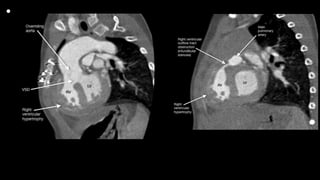

• “tetralogie” to refer to the

aggregate of four features

of the anatomy seen in the

majority of specimens coming

into his autopsy service from

patients with “la maladie

bleue”: pulmonary artery

stenosis, ventricular septal

communication, rightward

deviation of the aorta’s origin,

and hypertrophy of the right

ventricle

• Pathology

1. The original description of TOF included the

following four abnormalities: a large VSD,

RVOT obstruction, RVH, and overriding of the

aorta. In actuality, only two abnormalities are

required, a VSD large enough to equalize pressures

in both ventricles and an

RVOT obstruction. The RVH is secondary to the

RVOT obstruction, and the overriding

of the aorta varies